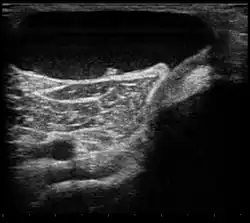

Ultrasound image of Baker's cyst | |

Diagnosis is by examination. A Baker's cyst is easier to see from behind with the patient standing with knees fully extended. It is most easily palpated (felt) with the knee partially flexed. Diagnosis is confirmed by ultrasonography, although if needed and there is no suspicion of a popliteal artery aneurysm then aspiration of synovial fluid from the cyst may be undertaken with care. An MRI image can reveal presence of a Baker's cyst.